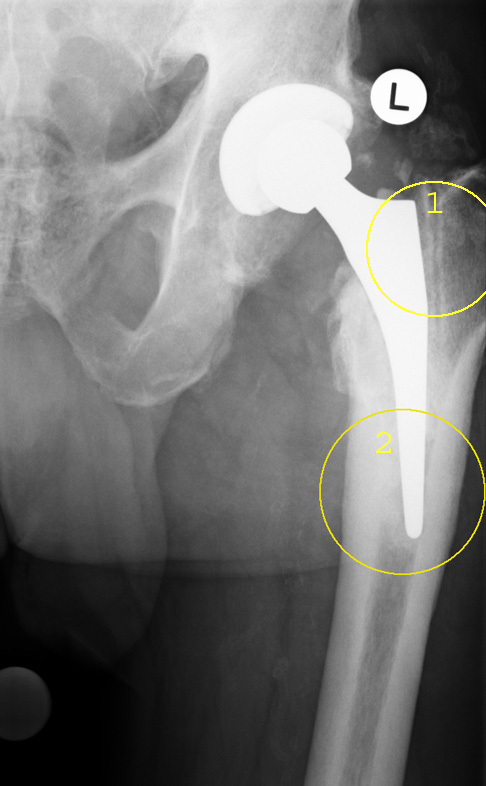

So lässt sich eine neue Prothese im Vergleich zur ersten meist deutlich schwerer im Knochen befestigen. Eine Ursache dafür ist die Immunreaktion des Körpers auf den Prothesenabrieb – Metall oder Plastik. Diese kann die Knochensubstanz schwächen und dadurch die Verankerung bei einem Prothesenwechsel erschweren (aseptische Osteolyse). Auch bestimmte Grunderkrankungen, wie z. B. Osteoporose können die Lebensdauer von Hüftprothesen begrenzen oder den Einbau einer Ersatzprothese schwierig gestalten.

- Die Tragfähigkeit des Beckenknochens unter der Gelenkpfanne oder im Markraum des Oberschenkelknochens (Femur) ist durch die vorangegangene Implantation der Prothese vermindert.

- Die Anatomie bzw. Form des Hüftgelenks kann durch Vorerkrankungen, Knochenschwund (Osteoporose) und Voroperationen verändert sein.

- Septische (bakterielle) oder aseptische (nichtbakterielle) Osteolyse kann die Knochensubstanz angreifen, sodass man alternative Verankerungsmethoden für die tragenden Prothesenbestandteile finden muss.

- Eine Schwäche des prothesentragenden Knochens kann den Aufbau mit Knochenersatzstoffen (Keramik, metallischer Knochenersatz) erforderlich machen, um eine sichere Verankerung zu erzielen.

- Knochendefekte als Folge von Osteolyse, Infektion oder Lockerung der Prothese können die sichere Verankerung einer Wechselprothese erschweren.